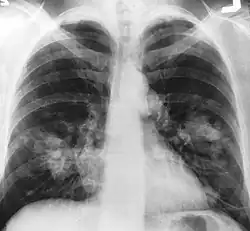

An X-ray scan indicating abnormal masses in the lungs. | |